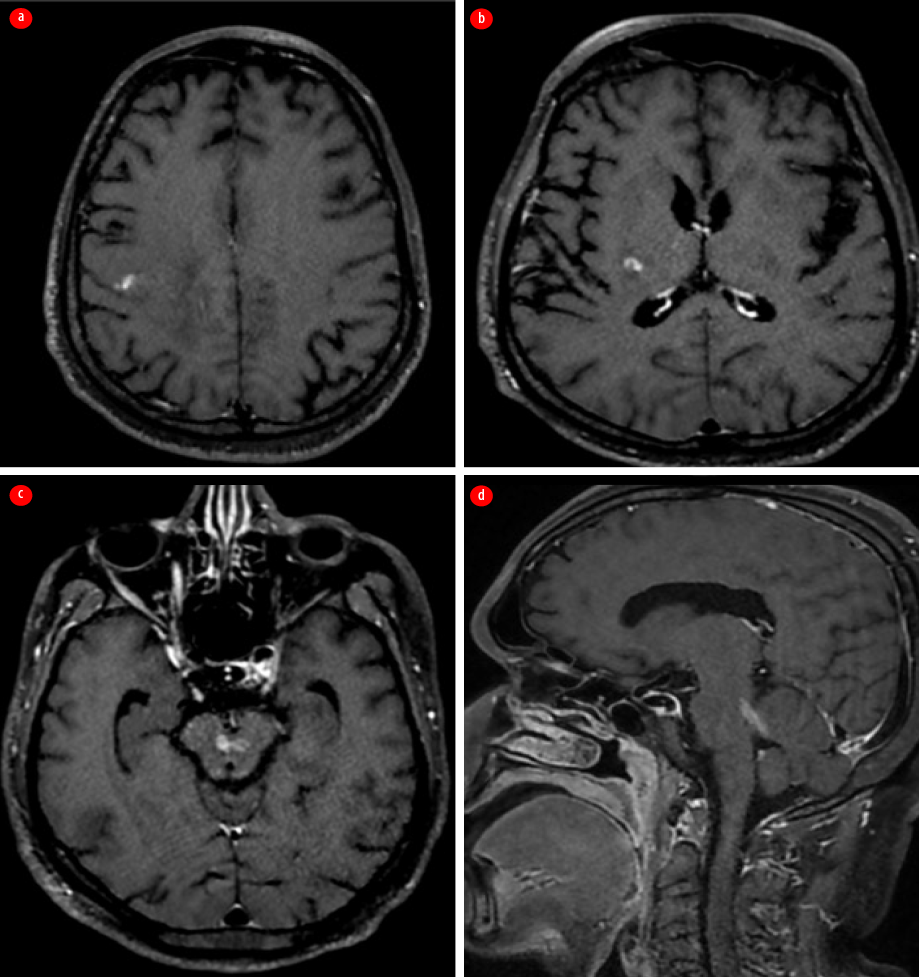

Two months later, while continuing the eradication treatment, the patient had another relapse and presented with headache and left focal motor seizures. A repeat contrast-enhanced MRI of the brain showed findings similar to the previous one, with additional edema in the ventral aspect of the medulla (more affected on the right side), which extended to the upper cervical cord, affecting the right spinothalamic and left lateral corticospinal tracts [Figure 4].

Figure 4: Repeated contrast-enhanced MRI after the second relapse. (a) Axial T2 fluid attenuated inversion recovery image. (b) Sagittal T2-weighted image shows new-onset hyperintensity involving the ventral aspect of pons and medulla.